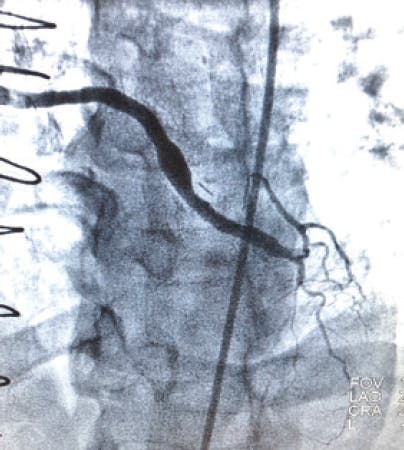

An Impella® device (Abiomed, Inc.) was placed emergently on arrival, and perfusion was restored. The initial angiogram showed an occlusion of the proximal left anterior descending (LAD) artery with an acute cutoff, consistent with thrombosis (Figure 1). The lesion was wired with a 0.014-inch balance middleweight wire (BMW; Abbott). CAT RX was used frontline, and flow was restored after two passes with 30 seconds of aspiration (Figure 2). The door-to-device time was 45 minutes. After mechanical thrombectomy, intravascular ultrasound was performed, revealing evidence of plaque rupture and minimal associated plaque burden. Primary stent implantation was therefore performed with a 3- X 28-mm DES, which was postdilated with a 3.25-mm noncompliant balloon to 18 atm. Final angiography revealed TIMI 3 flow with no evidence of distal embolization and restoration of myocardial blush (Figure 3). The Impella® device was removed at the end of the procedure. The patient experienced a full recovery and was discharged from the hospital after 3 days.

Figure 1. Initial angiogram showing occlusion of the proximal LAD.

Figure 2. Flow through LAD after mechanical thrombectomy with CAT RX.